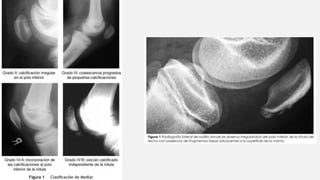

ENFERMEDAD DE OSGOOD SCHLATTER

Tracción repetitiva del

tubérculo tibia por el

cuadriceps, vía tendón

rotuliano

11 y 14 años de edad en los

hombres

Dolor a nivel de la

inserción distal del tendón

rotuliano, y edema. Uni-

bilateral

Rx fragmentación del

núcleo de osificación,

edema de tejidos blandos ,

engrosamiento del tendón

rotuliano y borramiento de

la grasa infrarotuliana

Evolución: recuperación

completa (tiempo variable)

Secuela: calcificación en el

extremo distal del tendón

Tto. ↓ carga deportiva,

suficiente tiempo de

descanso. Uso de soportes

del tendón rotuliano y

adecuada preparación física

predeportiva

ENFERMEDAD DE OSGOODSCHLATTER Tracción repetitiva del tubérculo tibia por el cuadriceps, vía tendón rotuliano 11 y 14 años de edad en los hombres Dolor a nivel de la inserción distal del tendón rotuliano, y edema. Uni- bilateral Rx fragmentación del núcleo de osificación, edema de tejidos blandos , engrosamiento del tendón rotuliano y borramiento de la grasa infrarotuliana Evolución: recuperación completa (tiempo variable) Secuela: calcificación en el extremo distal del tendón rotuliano Tto. ↓ carga deportiva, suficiente tiempo de descanso. Uso de soportes del tendón rotuliano y adecuada preparación física predeportiva